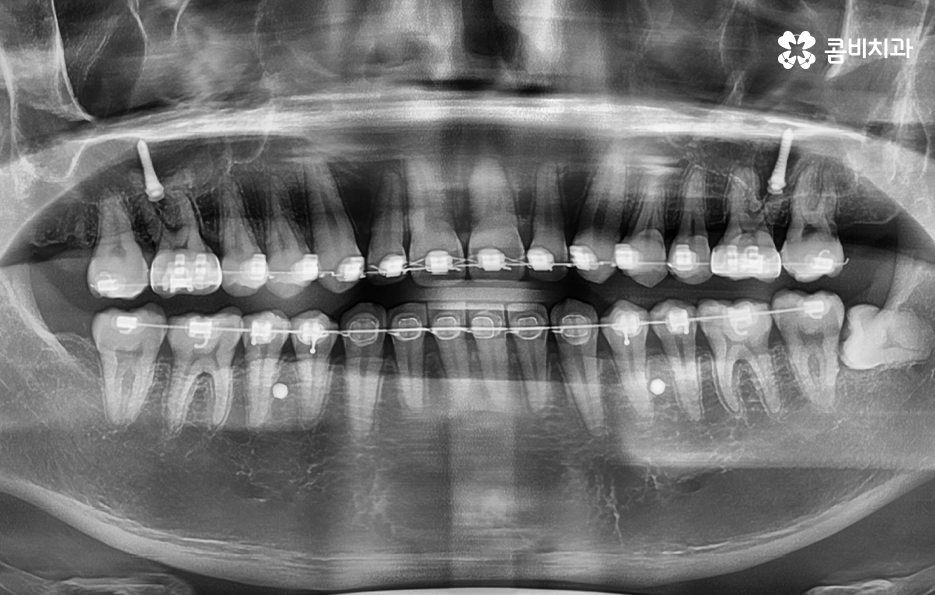

그리고 생각보다 많은 분들이 치아교정 전에 사랑니를 발치해야 하는지 궁금해 하시는 분들이 많은데 과거에는 교정 전에 꼭 충치 치료와 사랑니를 먼저 하고 치아교정을 진행했던 경우가 많았다고 할 수 있는데요

그 이유는 과거에는 교정은 교정 따로 사랑니 발치는 사랑니 발치 따로 치료가 진행되었던 경우가 많았기 때문에 지금처럼 협진이나 원스탑 진료 시스템이 잘 갖춰지지 않아서 교정 전에 사랑니 발치를 꼭 해야 했던 경우도 있었지만 현재는 각 개인의 상황에 따라서 교정 전에 하기도 하지만 교정 진행 중에 하기도 하고 교정이 끝난 후에 진행하는 경우도 있어요

이렇듯 사랑니 발치 시기 자체는 특정하게 정해져 있는 것은 아니고 각 개인의 상황과 치아 상태 등에 따라서 의사의 판단하에 결정되기 때문에 발치 자체에 대한 두려움으로 치과 방문을 미루실 필요는 없을 거예요